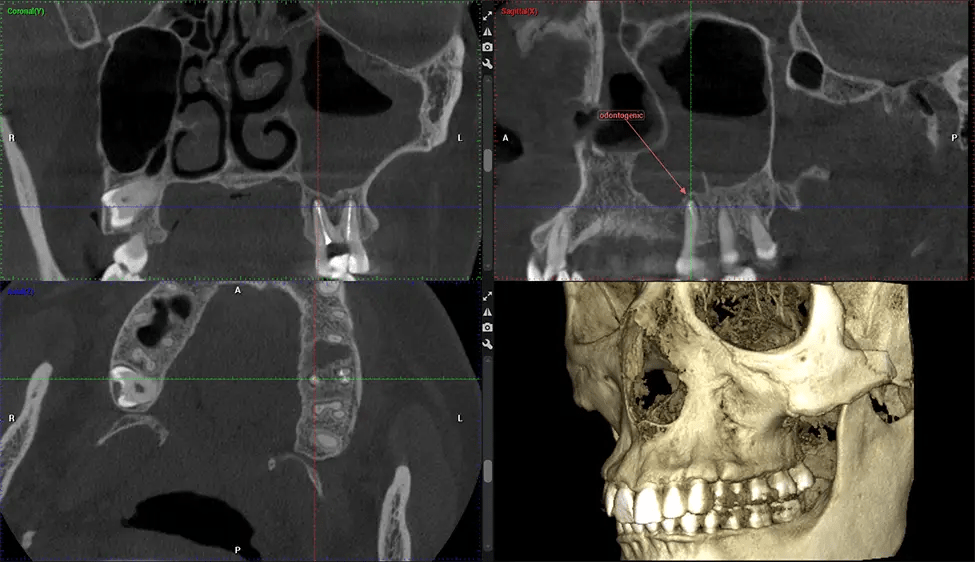

Cone Beam Computed Tomography (CBCT) is an advanced imaging technique used in dentistry and maxillofacial surgery to obtain detailed 3D images of the oral and maxillofacial structures. At Dr G Dental Studio, our CBCT scanners utilize a cone-shaped X-ray beam and a specialized detector to capture images from different angles. A computer then combines these images to create a 3D representation of the patient’s oral anatomy.

This 3D scan, called cone beam computed tomography, gives your dentist a more complete image of your oral anatomy and disease processes than a traditional X-ray. Unlike conventional X-rays, which capture a 2D image of your mouth from various angles, a 3D scan takes multiple digital X-rays for one image. It provides a complete view of your jaw, teeth, nerves, and soft tissues. This enhanced view allows dentists to detect minor issues not visible in traditional 2D scans, such as impacted wisdom teeth or bone fractures in the sinus cavity.

There are many benefits to using CBCT technology, especially compared to the traditional 2D X-ray format. One of the most significant advantages of CBCT scans is that they provide much more information than traditional X-rays. A scan lets your dentist see images from all angles of your jaw and mouth, including your sinuses, nasal cavity, cheekbones, and other surrounding areas. This added information helps your dentist craft a comprehensive treatment plan that addresses all aspects of your oral health.

Oral and Maxillofacial Surgeon Complex oral surgeries, orthognathic (jaw) surgery, and removal of impacted teeth. Offers precise, three-dimensional visualization of the skull, jaw, and craniocervical junction to enhance diagnostic accuracy and minimize surgical risks.

Orthodontist Assessing facial asymmetry, planning orthognathic surgery, and managing cleft lip and palate and sleep apnea. Provides a comprehensive view of the craniofacial complex to better plan treatments and evaluate outcomes.